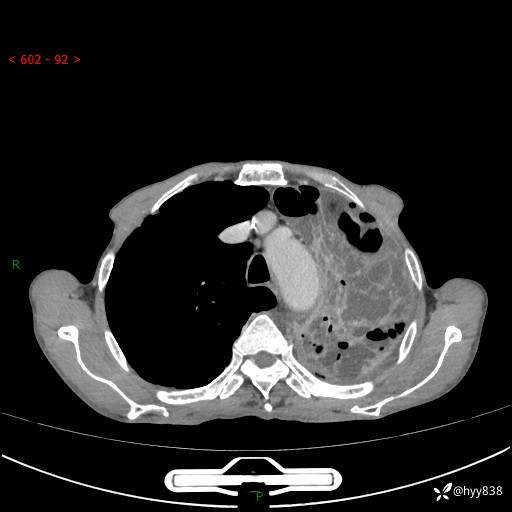

老年男性,反复咳嗽、咳痰、气喘10余年,再发3天。大叶性实变+胸膜病变-结果公布

胸部CT平扫+增强